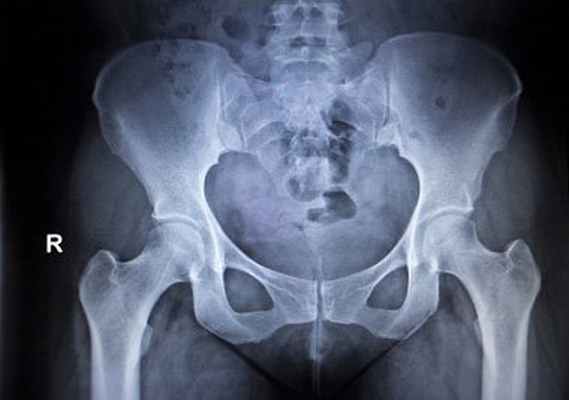

У детей старше 3х месяцев в дополнение к УЗИ-исследованию выполняется рентгенографическое исследование. До этого возраста лучевые методы исследования не являются информативными, поскольку отсутствует должная оссификация костных структур тазобедренного сустава и проведение их адекватной оценки крайне затруднено.

Предварительный диагноз часто выставляют в период пребывания в роддоме. В такой ситуации важно в ближайшие три недели посетить детского ортопеда. Необходимые диагностические процедуры — рентгенография и ультрасонография.

Малышам до 2-3 месяцев рентгенограмма не актуальна, поскольку большая часть сустава образована хрящами, не отображающимися на снимке. Новорожденным следует провести ультразвуковую диагностику, которая отличается повышенной безопасностью и информативностью.

Инструментальная диагностика

Методом выбора является рентгенография тазобедренного сустава в прямой и боковой проекциях. Это позволяет исключить переломы. Однако, в некоторых случаях, даже если рентгенологическая картина в норме, требуется проведение дополнительных исследований, например, КТ или МРТ тазобедренного сустава, с целью исключения скрытых переломов или повреждения мягких тканей.

В сложных случаях КТ может быть полезна для получения дополнительной информации, которая необходима при планировании операции. Также стоит учитывать, что интерпретация рентгеновского снимка будет осложнена у пожилых людей наличием других состояний, например, дегенеративных процессов.